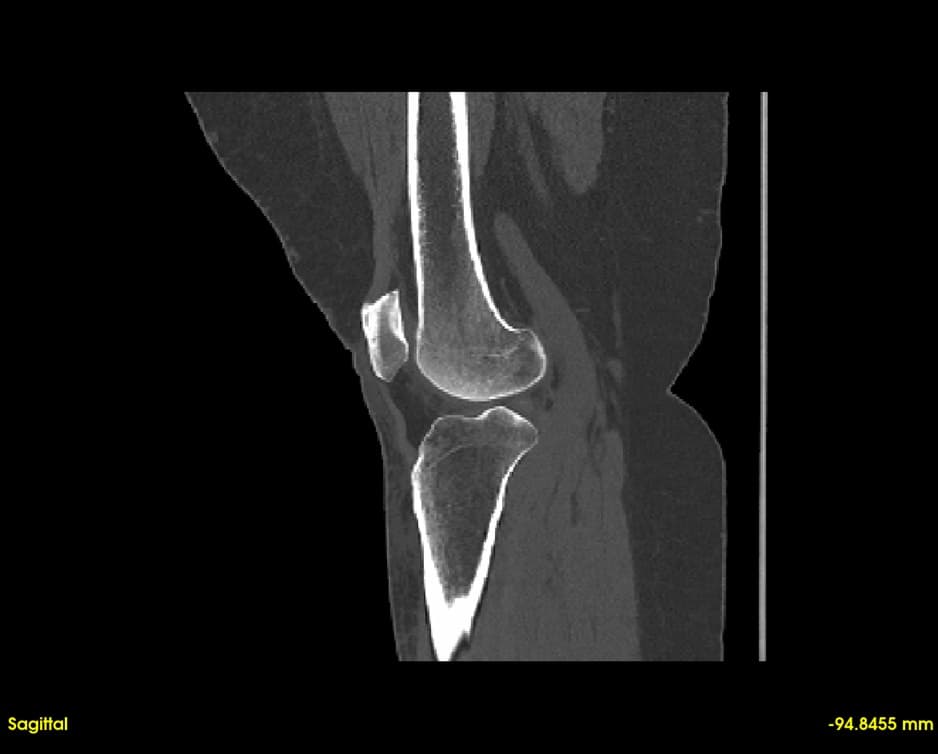

Simultaneous axial, sagittal, and coronal views. Navigate through slices with synchronized cross-referencing.

Explore slices with multi-planar reconstruction views

Quickly visualize and analyze anatomical structures from CT and MRI scans. Identify abnormalities with precise 3D visualization.